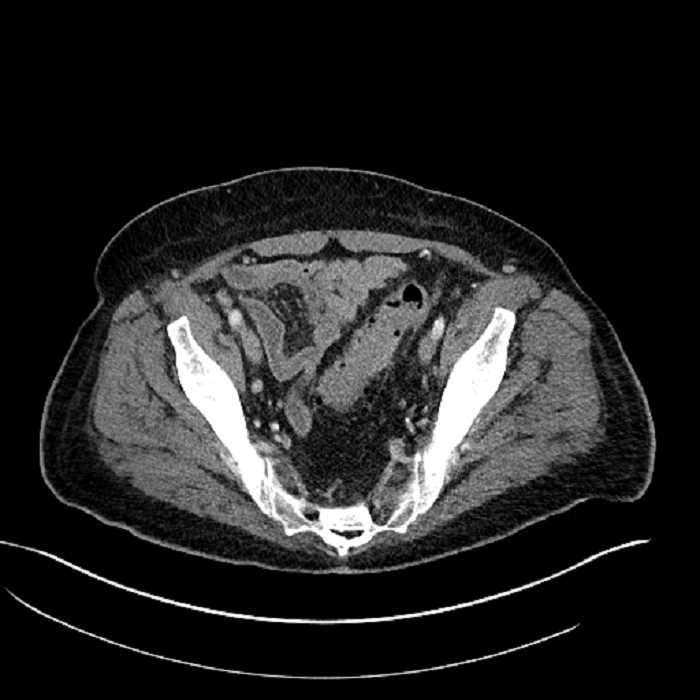

Age: 63

Sex: Male

Indication: Abdominal pain

• Mild mural thickening of a segment of the sigmoid colon with adjacent fat stranding and a 1.5 cm fluid and gas collection along the tip of an inflamed diverticulum

• Loss of the normal fat plane between this collection and adjacent loops of small bowel, which demonstrate mural thickening

• No bowel obstruction

Acute sigmoid diverticulitis complicated by a small contained perforation and a large abscess in the right hepatic lobe. Additional small subcapsular abscesses along the anterior margin of the left hepatic lobe.

Additionally, loss of the normal fat plane between the peridiverticular collection and adjacent thickened loops of small bowel raises the potential for an enterocolonic fistula.

Hepatic abscess showing the double target sign with low density internally surrounded by a thin inner enhancing rim (red arrow) and ill-defined outer low density rim (yellow arrow). Blue arrow indicates an internal septation. Red arrows: additional smaller subcapsular abscesses. Red arrow: focal contained perforation associated with diverticulitis.